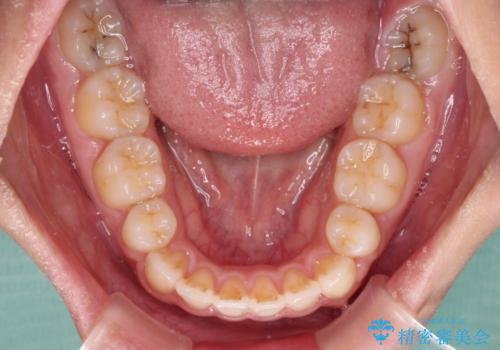

- 前歯のデコボコと口元の突出感を気にして来院された患者様です。

上下左右第一小臼歯4本を抜歯し、ワイヤー装置にて口元を引っ込めるよう矯正治療を行うこととしました。

非常にスムーズに歯列移動が行われ、当初は2-2.5年を予想していましたが、僅か1年4ヶ月で治療を終えることができました。